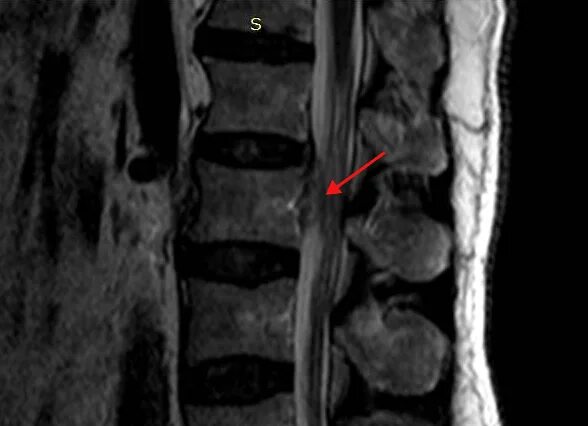

Как выглядит грыжа позвоночника на мрт